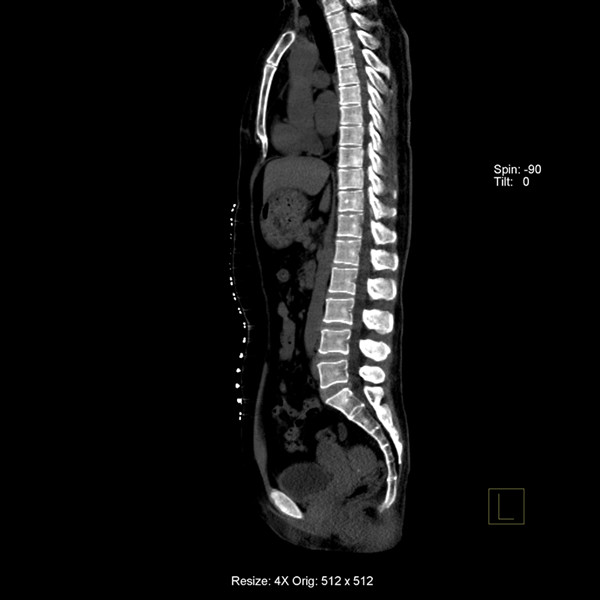

炫速雙源CT是目前世界上最先進的CT設(shè)備之一。它采用兩套64排圖像采集系統(tǒng),結(jié)合“飛焦點”技術(shù),并且有超高的旋轉(zhuǎn)速度,能夠在極短的時間內(nèi)完成掃描,為病人提供“綠色” CT 檢查。它的特點是炫速掃描技術(shù) (Flash Spiral),即大螺距的螺旋掃描,可以在一秒鐘之內(nèi)完成掃描,同時輻射劑量極低。 它的主要特色掃描技術(shù)如下:

炫速全胸掃描  完成全胸掃描(包括心臟冠脈在內(nèi))僅需 0.6 s,患者可無需屏氣;可實現(xiàn)業(yè)界最大范圍-48 cm的四維功能成像,實現(xiàn)了亞 mSv 級“綠色”心臟成像。

75ms的時間分辨率以及高達 43 cm/s 的掃描速度使患者無需服用β-受體阻滯劑控制心率,并首次實現(xiàn)了無需屏氣的亞 mSv 級“綠色”心臟成像。

7、病人因胸痛急診時,快速獲得準(zhǔn)確的診斷是關(guān)鍵。對于具有極高時間分辨率的炫速雙源CT來說,不但可以輕松完成常規(guī)檢查,而且可以對特別嚴(yán)重的急診患者完成“一站式”診斷,對急性胸痛患者通過一次注射對比劑同時獲得冠脈CTA、肺動脈CTA及主動脈CTA,可明確胸痛病因是心臟冠脈疾病、肺動脈栓塞還是主動脈夾層,具有非常實用的臨床價值。